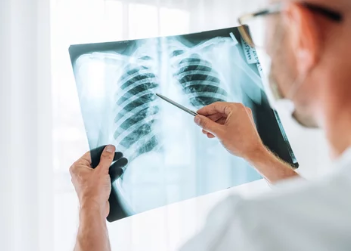

결핵은 흉부 X-ray 검사, 객담 검사, 결핵균 PCR 검사 등을 통해 진단할 수 있습니다.

- 흉부 X-ray 검사: 폐결핵 여부를 확인하기 위해 흉부 X-ray 검사를 시행합니다. 흉부 X-ray 검사에서 이상 소견이 발견되면 추가 검사를 시행합니다.